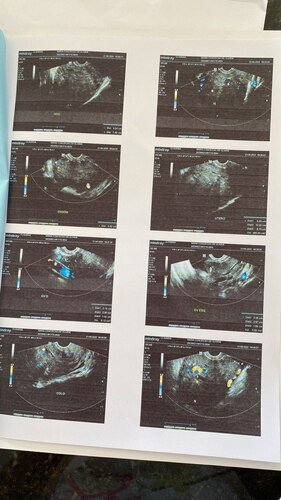

01 - Cirurgia um mioma que está entre o útero e o intestino e isso me impede de defecar, causando desconforto e ressecamento.

O mioma está crescendo muito rápido porque o meu sangramento é muito intenso e o sangue faz com que ele cresça e desenvolva com muita rapidez, pois já está quase uma gestação de cinco meses empurrando o intestino e o útero que aumentou de tamanho.

E foi quando descobri a pedra na vesícula fazendo os exames sendo assim mais uma cirurgia a ser feita.

02 - Cirurgia de pedra na vesícula, que ao realizar o exame de ultrassom apresentou.